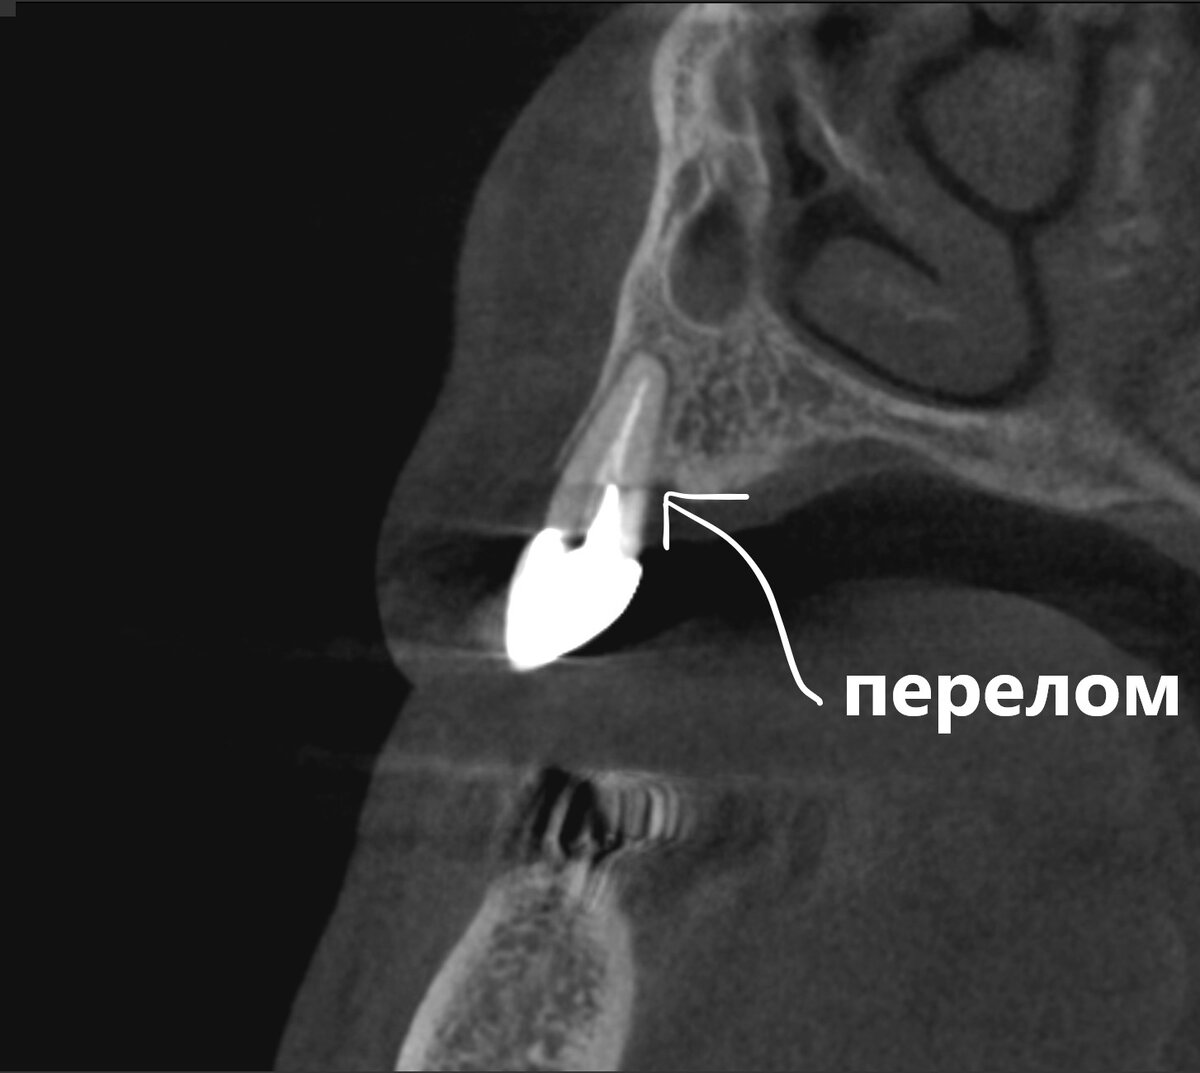

Посмотрим срезы КЛКТ.

Листайте - там все 6 зубов (один выложу аж 2 раза - для пущей убедительности).

Кто-то, конечно, скажет - хорошие зубы! С ума сошли, удалять такое сокровище.

А я скажу - всё это скоро само выпадет. Один нормальный зуб в поле не воин и не стоит того, что бы из-за него прибегать к более сложной и дорогостоящей реабилитации.